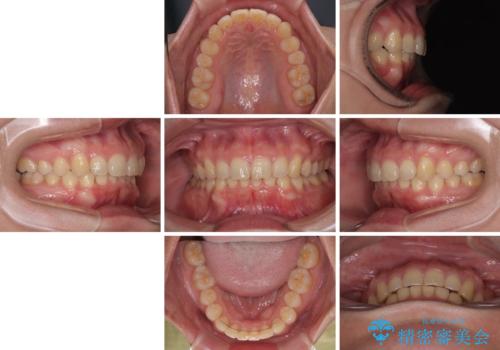

隠れた前歯が気になる ディープバイトのワイヤー矯正治療

- 下顎前歯が完全に隠れてしまっていることを気にして来院された患者様です。

下顎の臼歯が手前に傾斜していることで咬み合わせが深くなってしまい、下顎前歯が見えないほどに上顎前歯が覆い被さっている状態でした。

下顎臼歯を起き上がらせるためにユーティリティーアーチを使用し、一気に深い咬み合わせを改善することができました。